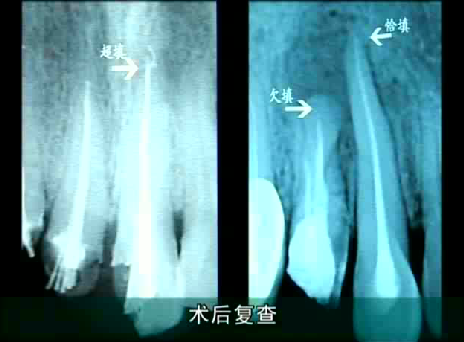

1、比如,和醫生技術有關(guan) 係。有的醫生臨(lin) 床經驗豐(feng) 富,對於(yu) 根管治療通常可以熟練操作,不會(hui) 出現超充或者欠充等情況,治療完成後出現複發的幾率自然比新手醫生更低一些。

根管治療超充、欠充在牙片上的顯示

比如如果是根管超充或者是欠充,需要拆掉牙冠,重新根管治療,擴大根充,盡量接近根尖,對於(yu) 牙根彎曲或者過細疏通不了的,可以塑化治療。